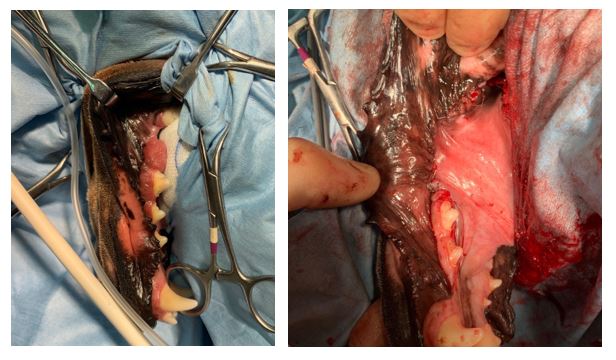

1. Repairing a bilateral fractures to the rostral mandible

After a collision with a park bench, this patient suffered bilateral fractures to the rostral mandible and both mandibular canine teeth were dislocated. In order to preserve the patient’s teeth and maintain a normal occlusion, the canine teeth were repositioned and a wire and acrylic splint applied.

The soft tissue lacerations were also sutured. A transmylohyoid intubation was performed to aid access and monitor the occlusion during the placement of the splint. This will be re-evaluated in 4 weeks to check healing and determine if the canine teeth are still vital. Luxated/ avulsed teeth must receive re-implantation treatment in less than 72 hours to have a good success rate of continuing to be vital teeth.